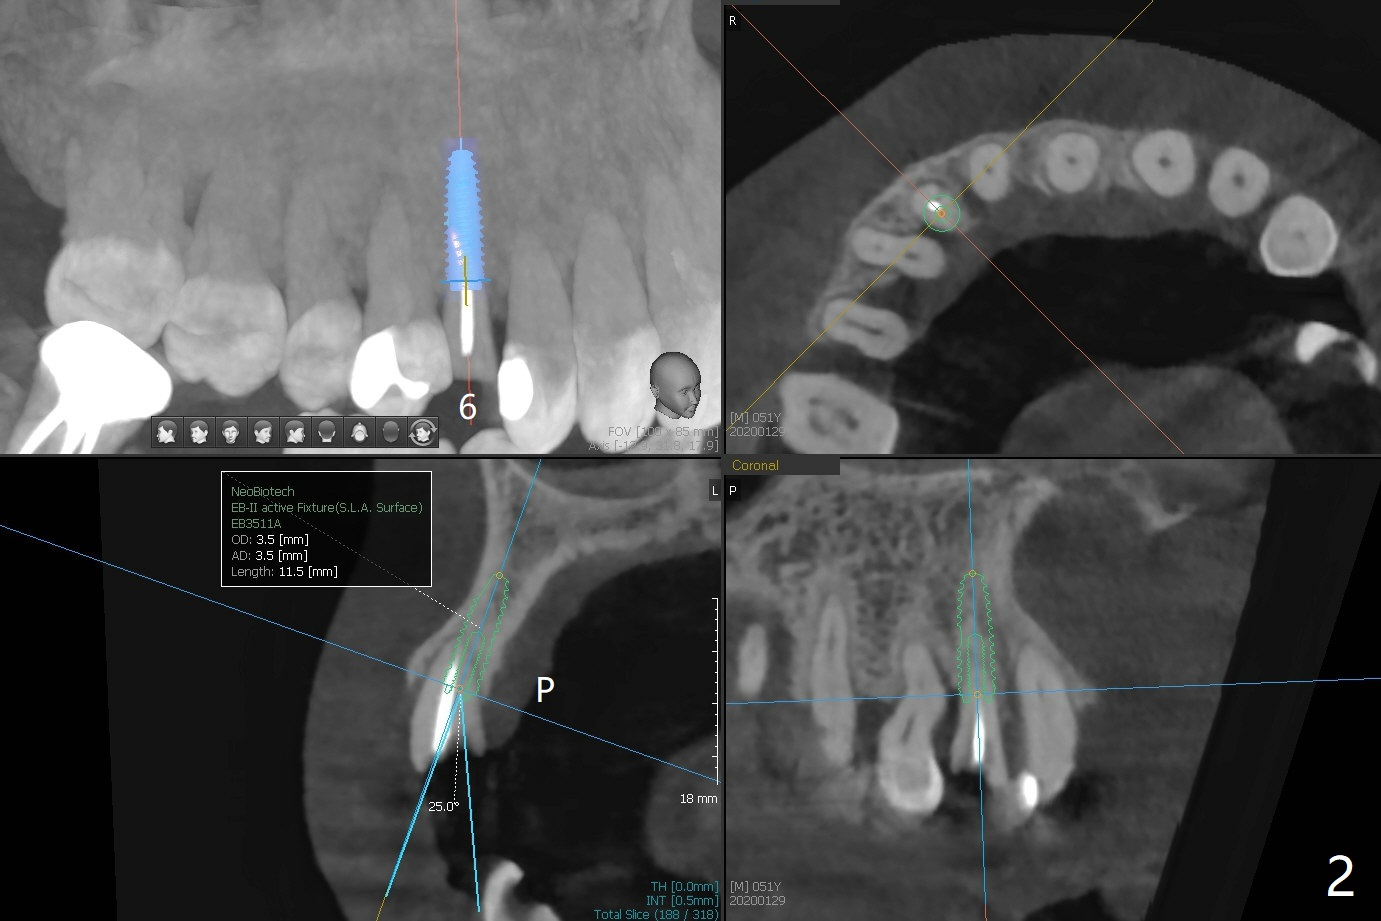

A 51-year-old man with chronic periodontitis requests implants at 19, 24-26 and 30 nearly 2 months post extraction without bone graft (Fig.1). He is willing to quit smoking by using electronic smoke. After SRP, the tooth #6 with supragingival fracture will be saved by post and crown. The mesiodistal space seems to be too narrow for implant (Fig.2). 1-piece implants will be placed at #24 and 26 for FPD (Fig.3,4). Implant placement at #19 and 30 will involve incision, socket redebridement, guide, bone graft (sticky bone), PRF membranes as a barrier and sutures (Fig.5,6).